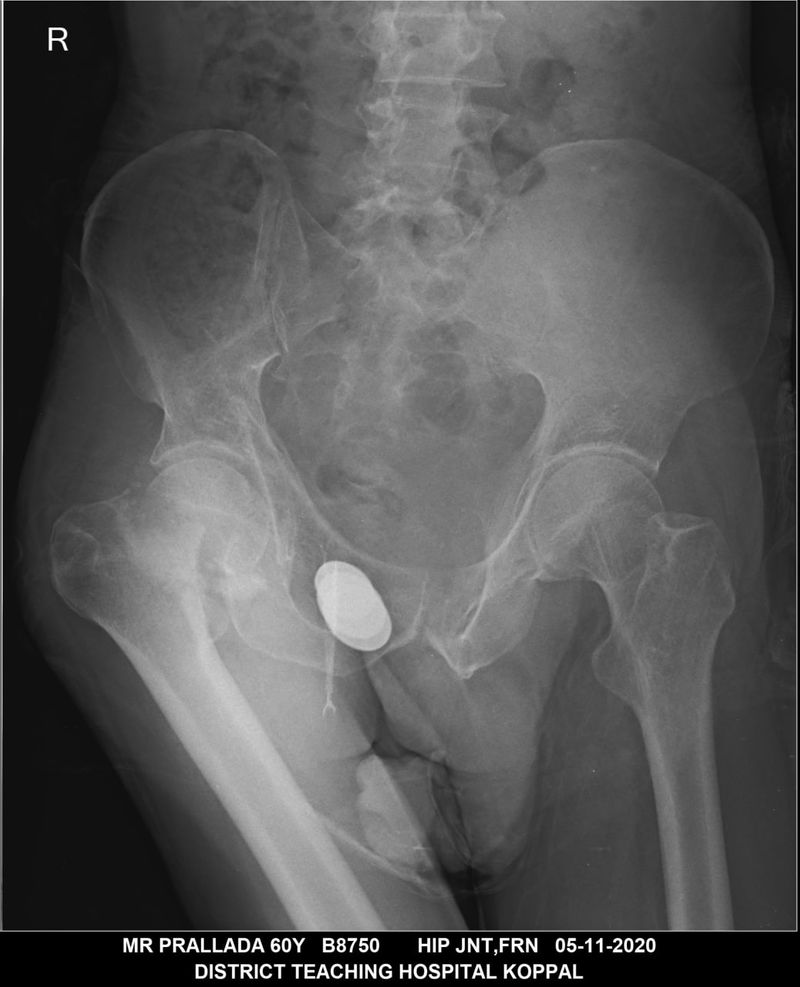

ಮೆಡಿಕಲ್ ಕಾಲೇಜು ನಿರ್ದೇಶಕ ವೈಜನಾಥ ಇಟಗಿ ಅವರು ಎಲುಬು ಕೀಲು ತಜ್ಞ ವೈದ್ಯ ಡಾ. ವಿಜಯ ಸುಂಕದ್ ಅವರೊಂದಿಗೆ ಚರ್ಚಿಸಿ, ಅನಾಥರಾಗಿರುವುದರಿಂದ ದಾಖಲೆ ಇಲ್ಲದೆ ಇರುವುದು ಸಮಸ್ಯೆಯಾಗುತ್ತದೆ. ಆದರೂ ಮೆಡಿಕಲ್ ಕಾಲೇಜಿನಲ್ಲಿ ಇರುವ ವಿಶೇಷ ನಿಧಿಯನ್ನೇ ಬಳಕೆ ಮಾಡಿಕೊಂಡು ಆಪರೇಷನ್ ಮಾಡಿಸಲು ನಿರ್ಧರಿಸಲಾಗುತ್ತದೆ. ಹದಿನೈದು ದಿನಗಳ ಹಿಂದೆಯೇ ಆಪರೇಷನ್ ಮಾಡಲಾಗಿದ್ದು, ಸಂಪೂರ್ಣ ಗುಣಮುಖರಾಗಿದ್ದು, ಈಗ ವಾಕರ್ ಹಿಡಿದುಕೊಂಡು ನಡೆದಾಡುತ್ತಿದ್ದಾರೆ. ಚಪ್ಪೆಯ ಆಪರೇಷನ್ ಮಾಡಲಾಗಿದ್ದು, ಮುರಿದಿದ್ದ ಚಪ್ಪೆಯ ಗುಂಡನ್ನೇ ತೆಗೆದು ಕೃತಕ ಗುಂಡನ್ನು ಅಳವಡಿಸಲಾಗಿದೆ.

ಅನಾಥನಾಗಿದ್ದರಿಂದ ದಾಖಲೆಗಳು ಇರಲಿಲ್ಲ. ಆದರೂ ಮೆಡಿಕಲ್ ಕಾಲೇಜು ನಿರ್ದೇಶಕರ ಸಹಕಾರದಿಂದ ಆಪರೇಷನ್ ಮಾಡಲಾಗಿದೆ. ವಾಕರ್ ಸಹಾಯದಿಂದ ನಡೆದಾಡುತ್ತಿದ್ದಾನೆ. ಅನಾಥನನ್ನು ಆಸ್ಪತ್ರೆಯ ಸಿಬ್ಬಂದಿಯೇ ಮನೆಯ ಸಂಬಂಧಿ ಎನ್ನುವಂತೆ ನೋಡಿಕೊಂಡಿದ್ದಾರೆ ಎಂದು ಎಲಬು, ಕೀಲು ತಜ್ಞವೈದ್ಯ ಡಾ. ವಿಜಯ ಸುಂಕದ್ ತಿಳಿಸಿದ್ದಾರೆ.